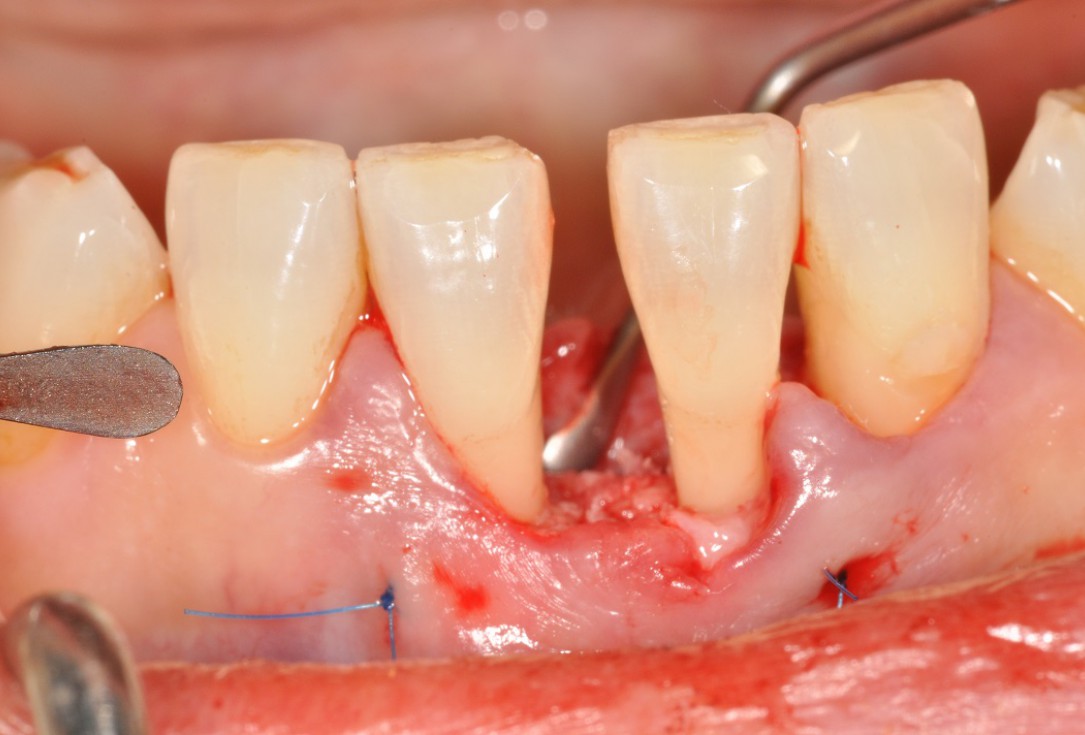

03/13 - Flap elevation and presentation of the defect.

Wide intrabony defect treated with the modified papilla preservation flap in conjunction with Straumann® Emdogain® and autogenous bone - Dr. B. Molnar